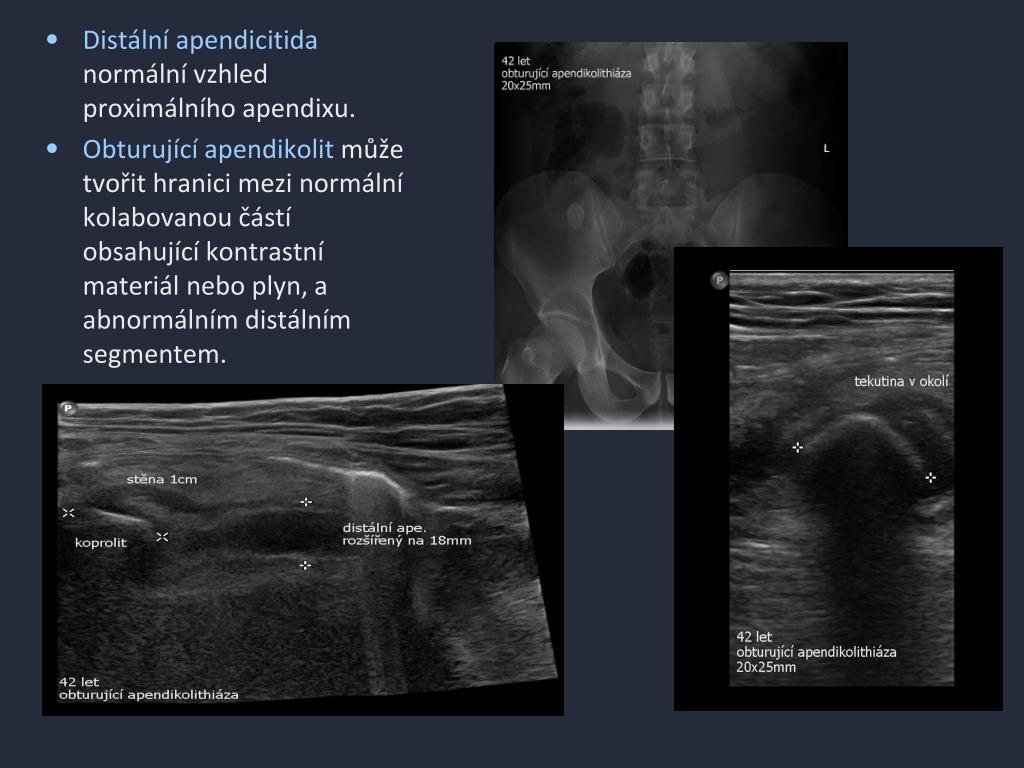

10. Distální apendicitida normální vzhledproximálního apendixu. • Obturující apendikolit může tvořit hranici mezi normální kolabovanou částí obsahující kontrastní materiál nebo plyn, a abnormálním distálním segmentem.